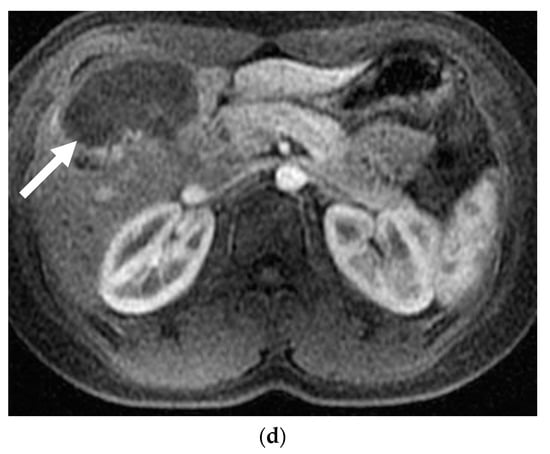

Figure 2.

A 24-year-old female with focal nodular hyperplasia (FNH) and right upper quadrant pain. (a) Magnetic resonance imaging (MRI) with contrast demonstrates a hypervascular lesion in segments 4 and 5 (solid white arrow). Twenty-minute delayed images showed continued enhancement (not shown). (b) Angiogram reveals segment 4 and segment 5 arteries that feed a hypervascular mass. Each artery was infused with 200 and 300 µm PVA particles until stasis. (c) Post-embolization angiogram shows no flow to the FNH. (d) MRI with contrast one month after embolization reveals no residual enhancement and a decrease in the size of the FNH (solid white arrow). The patient’s pain resolved following the embolization.